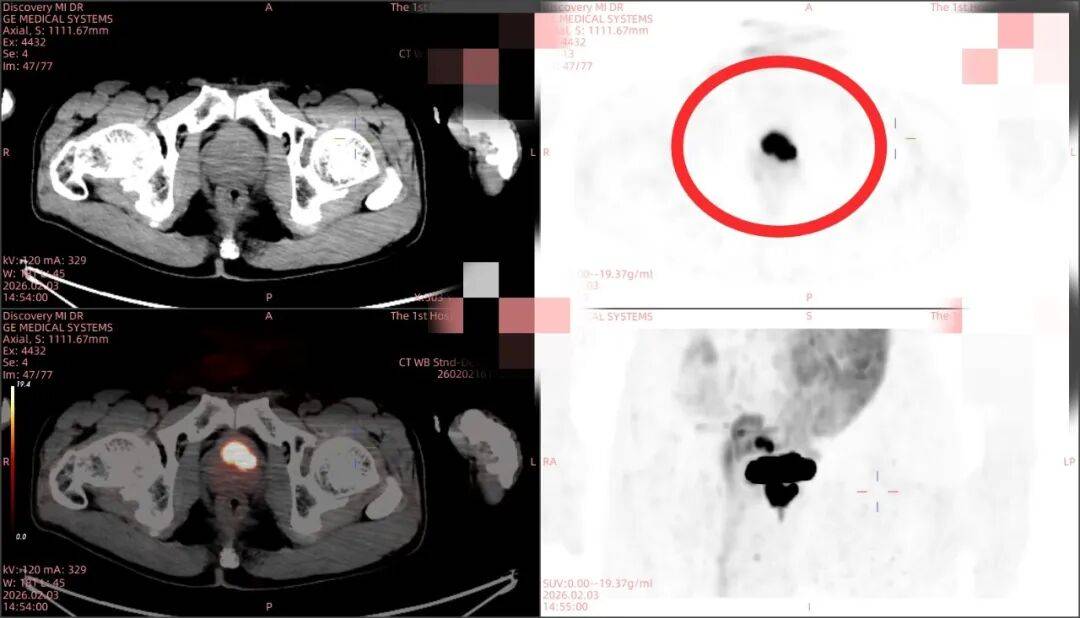

随后,团队副主任技师胡兵为庞大爷启动了针对性更强的PSMA-PET/CT显像检查。PSMA提示前列腺前纤维肌肉基质部及左侧移形带病灶高攝取,精准锁定恶性病灶,右侧外周带未见异常摄取提示前列腺炎,成功“命中”了此前隐匿的肿瘤病灶。

PSMA精准定位前列腺前纤维肌肉基质部及左侧移形带为前列腺癌病灶,右侧外周带未见异常摄取提示前列腺炎

拿着这份精准的检查报告,庞大爷一家人的“谜团”终于水落石出。这一次,医生依据PSMA显像提供的“精准坐标”,检查结果与此前格里森6分的前列腺癌诊断完全吻合。“PSMA显像就像给穿刺手术装了‘导航系统’,让我们告别了‘盲穿’,既提高了穿刺的阳性率,也减少了患者的创伤。”我院泌尿外科郭宇琛医生表示,明确的病灶定位为后续制定“主动监测”的治疗方案提供了坚实依据。